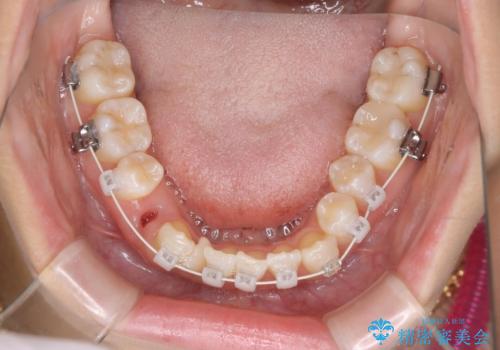

- 八重歯と叢生を主訴に来院されました。なるべく健康な歯を残したいという患者様の希望から、右側上下4番抜歯をしてワイヤー矯正する治療計画を立てました。

なるべく健康な歯を残したいという患者様の希望から、右側上下4番抜歯をして矯正しました。片側抜歯だったため、正中がズレないように気をつけながら治療を行いました。